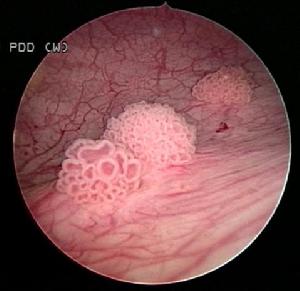

(1)移行上皮性腫瘤:主要包括原位癌、乳頭狀瘤、乳頭狀癌及實體性癌。後兩者可在一個腫瘤同時出現,稱為乳頭狀實體性癌。這種分類便於臨床套用,但從腫瘤生物行為來說,它們是一個病的不同階段的連續發展還是在開始時就獨自出現,是很有爭論的問題。

b.乳頭狀瘤,是一良性腫瘤組織學上可見腫瘤源起於正常膀胱黏膜,像水草樣突入膀胱內,具有細長的蒂,其中可見清楚的纖維組織及血管的中心束。乳頭狀瘤有復發的特點,5年內復發率為60%,其中48.6%復發兩次以上。術後有必要定期膀胱鏡隨診。

c.乳頭狀癌,在移行上皮性腫瘤中最常見。病理特點是,各乳頭粗短融合,瘤表面不光潔,壞死或有鈣鹽沉著,瘤基底寬或蒂粗短。有時乳頭狀癌或長如小拳,但仍保留一蒂,對其他部位無浸潤。此形雖不多見,但應注意,以免作不必要的全膀胱切除術。